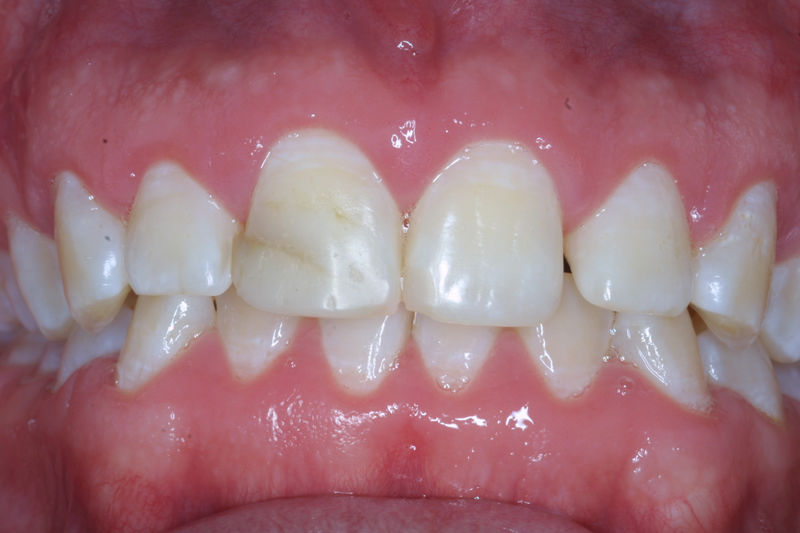

Amplia gama de tratamientos para mejorar la apariencia de la sonrisa, corrigiendo el color, la forma, el tamaño, la alineación y la posición de los dientes. Los procedimientos más comunes y solicitados incluyen el blanqueamiento dental, las carillas y coronas, así como las resinas.

Son restauraciones que cubren toda la cara frontal del diente, generalmente empleadas en el sector anterior y cuya finalidad es primariamente estética.

Ortodoncia y coronas.